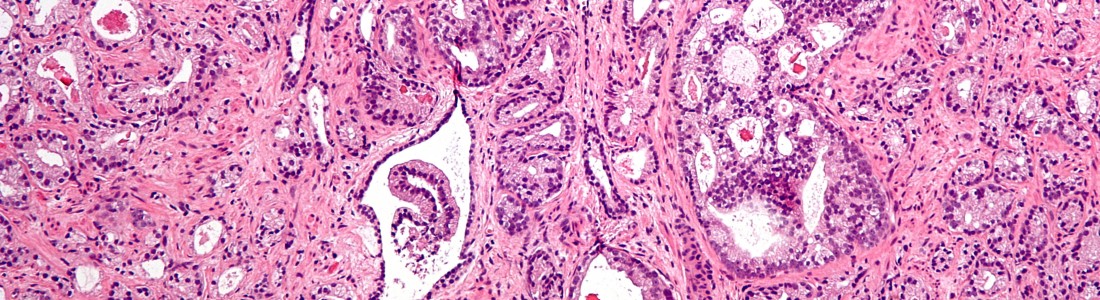

Омега-3 вызывают рак простаты - фото презентация